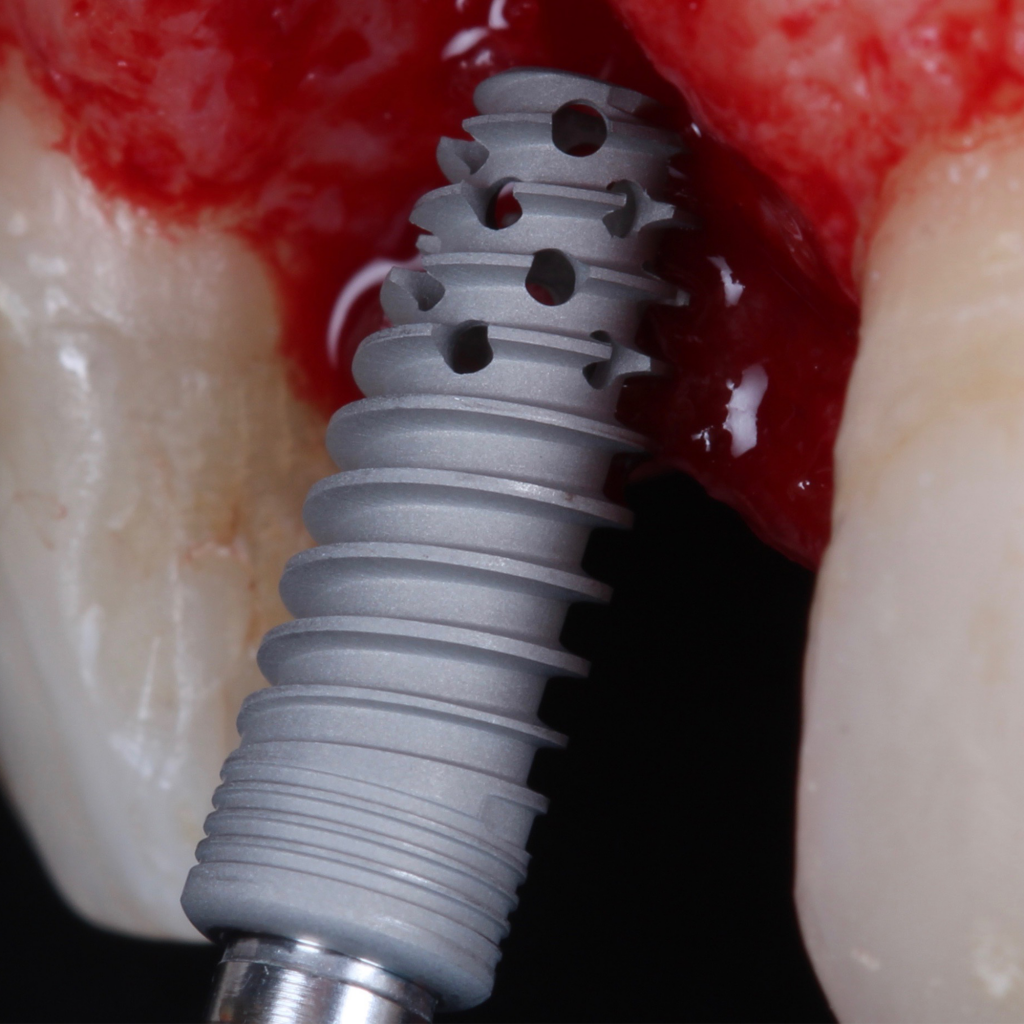

Desde 1985 tenho colaborado com o professor Per-Ingvar Brånemark e nos últimos anos, desenvolvi, juntamente com ele e Christian Brånemark, uma nova macro geometria do ápice do implante. Está parte apical do implante tem a função de reduzir o atrito, devido a seu corte preciso, controlando o torque de inserção, coletando lascas de tecido ósseo para o interior da câmara apical.

Since 1985 I have been collaborating with professor Per-Ingvar Brånemark and during the last years, I have, together with him and Christian Brånemark, developed a new implant tip.This part of the implant is reducing friction, due to precise cutting, reducing insertion torque and collecting bone chips inside the tip part of